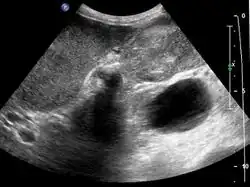

Early diagnosis is not generally possible. People at high risk, such as women or Native Americans with gallstones, are evaluated closely. Transabdominal ultrasound, CT scan, endoscopic ultrasound, MRI, and MR cholangio-pancreatography (MRCP) can be used for diagnosis. A large number of gallbladder cancers are found incidentally in patients being evaluated for cholelithiasis, or gallstone formation, which is far more common.[13] A biopsy is the only certain way to tell whether or not the tumorous growth is malignant.[14]

Gallbladder carcinoma

Gallbladder carcinoma on ultrasound